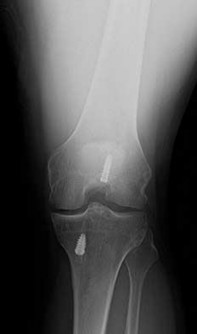

What is the most likely explanation for the change between the initial intraoperative radiograph (Figure 11a) and the radiograph taken 4 weeks after surgery (Figure 11b) in an 87-year-old man who underwent primary hip replacement for osteoarthritis?

The image demonstrates subsidence of the femoral implant. The implant subsided because it did not have good initial stability. The tapered femoral implant was placed after initial preparation for an anatomic femoral stem. A limited, nondisplaced femoral neck fracture was encountered during the procedure and treated. Two advantages of tapered stems are the efficient transfer of stress to the proximal femur and the ability to accommodate some subsidence to achieve enhanced stability. Although subsidence of a tapered stem to a more stable position can produce a good result, quality of metaphyseal bone should be considered. Attention to surgical technique remains important to optimize component stability for biological fixation.